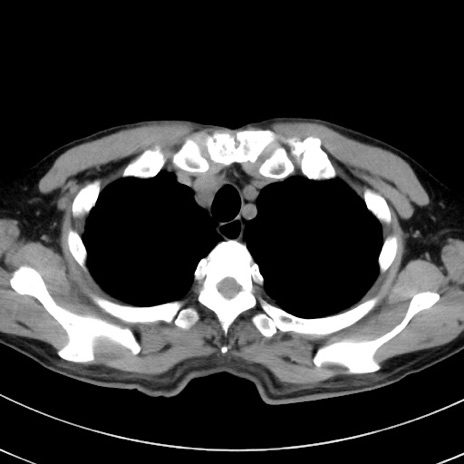

冠状断像